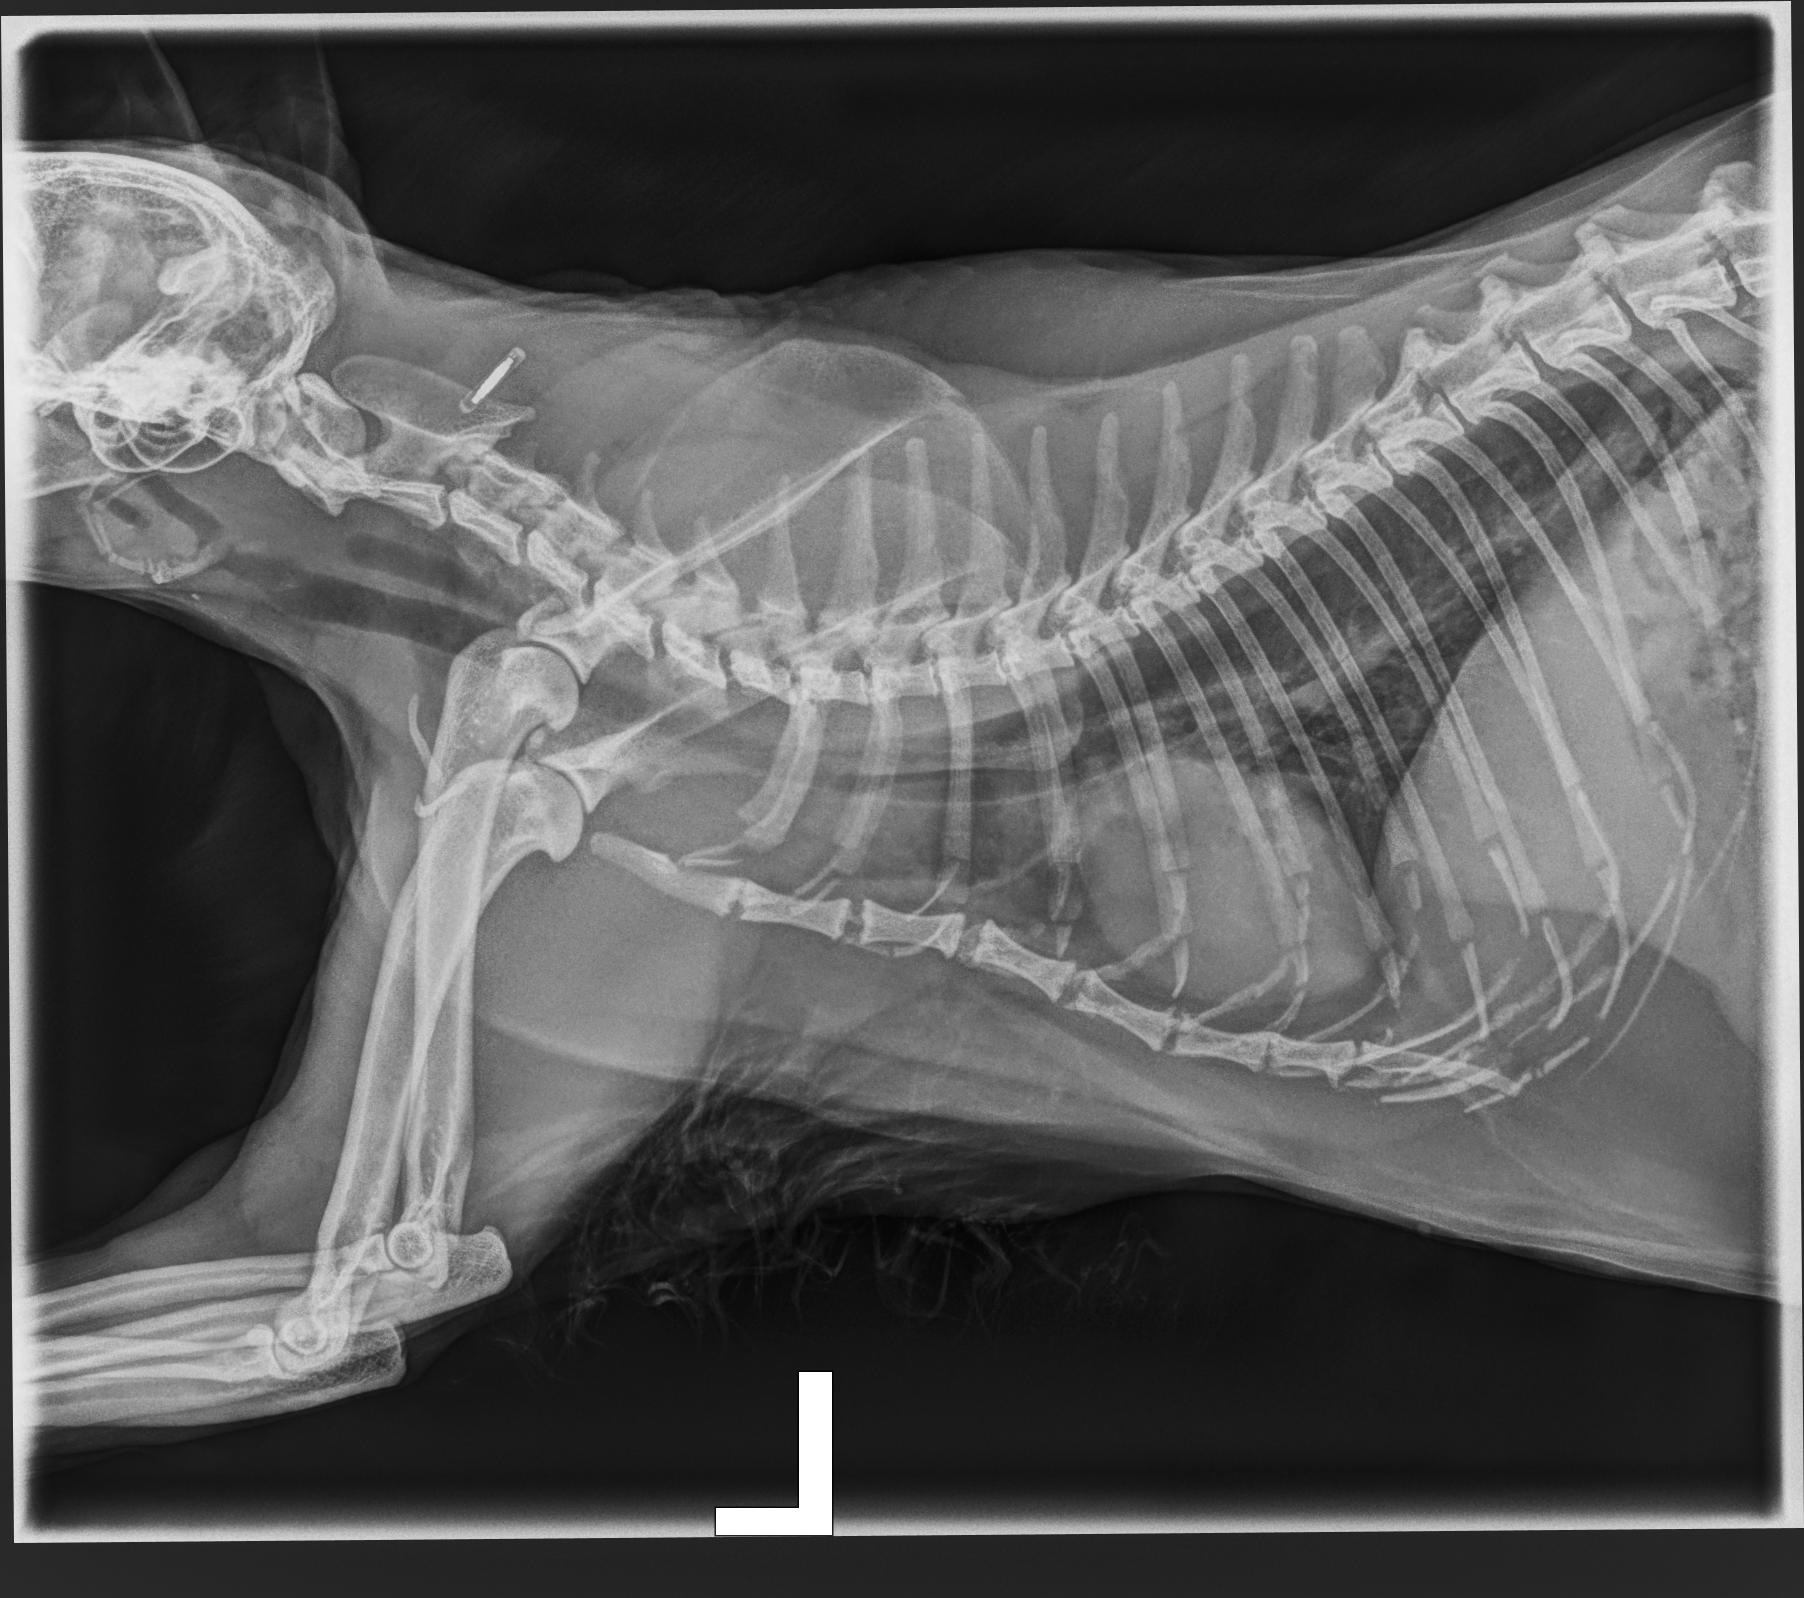

Cas clinique d’une chirurgie orthopédique : protocole et prise en charge suggérée

- Rappel des conséquences du syndrome brachycéphale sur la gestion de l’anesthésie

- Proposition d’un protocole de gestion de l’anesthésie pour les brachycéphales

- Discussion sur les points de débat autour de la gestion des brachycéphales